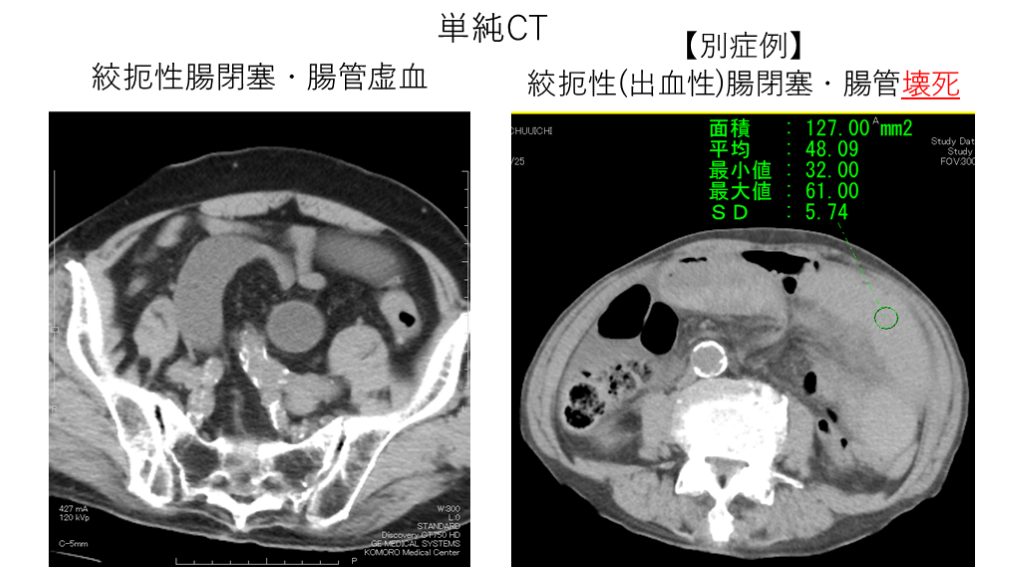

絞扼性腸閉塞・腸管虚血 絞扼性(出血性)腸閉塞・腸管壊死 単純CT 【別症例】

#11.

絞扼性腸閉塞・腸管虚血 絞扼性腸閉塞・腸管壊死 【別症例】

Take home message ・絞扼性腸閉塞は造影効果が保たれていても手術適応。  単純CTと造影CT(早期・後期)の“比較“が大切。 ・何よりもclosed loopを見つけることが重要。(気力が必要)   ①口側の拡張した腸管   ②腸管の先細り像(caliver change) ×2   ③肛門側の虚脱した腸管    上記を見つければ絞扼起点が近い。 ・読影に不安であれば経過観察入院を。